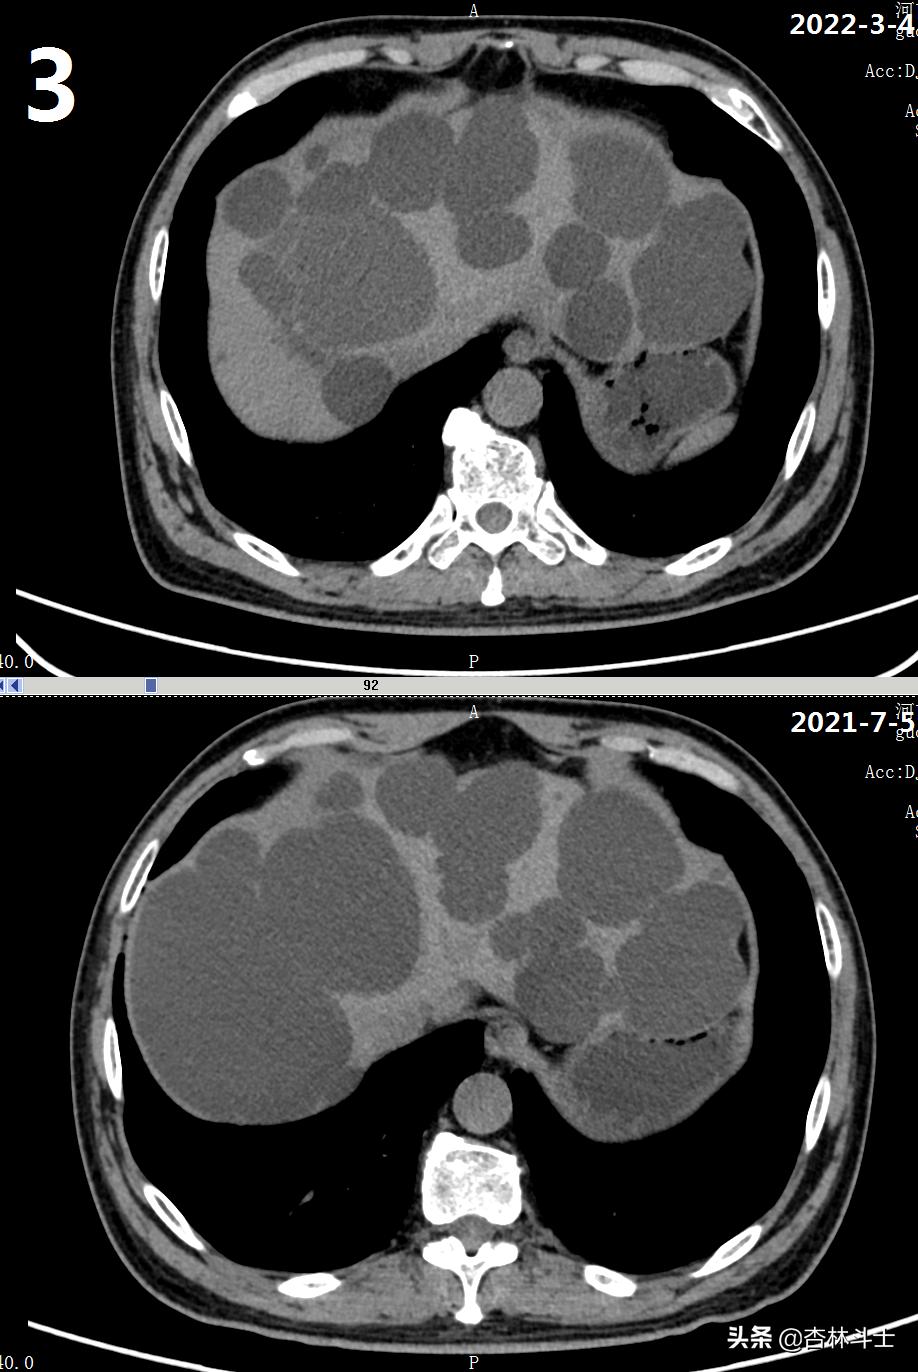

64岁退休银行职员,腹胀5年,加重2月,第二次入住我院消化内科。下图1-6为本次复查上腹部CT与2021-7-5肝囊肿经皮肝穿刺抽吸无水酒精硬化术前的对比图。

可明显看出,肝内囊肿较前减少,肝实质所占体积明显增加。